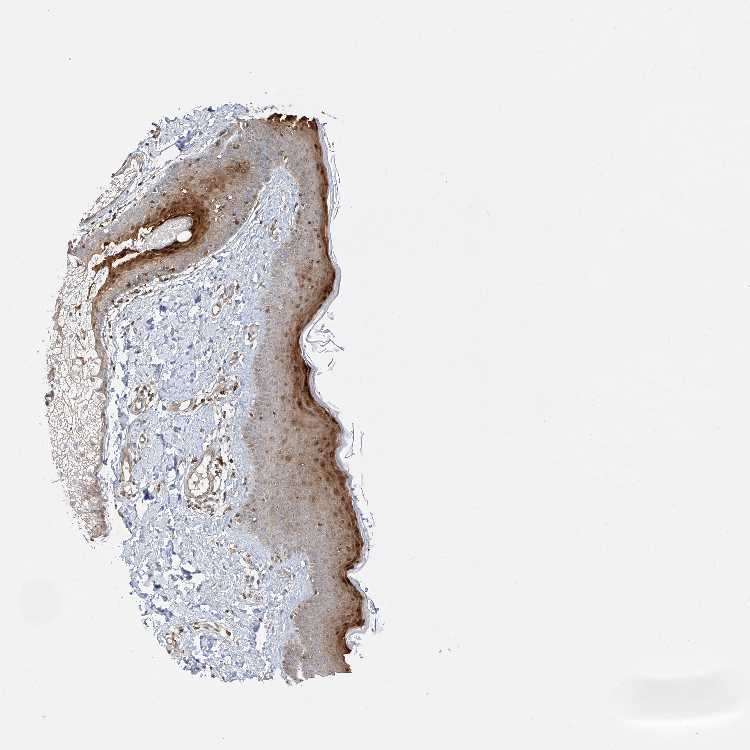

PLPP3